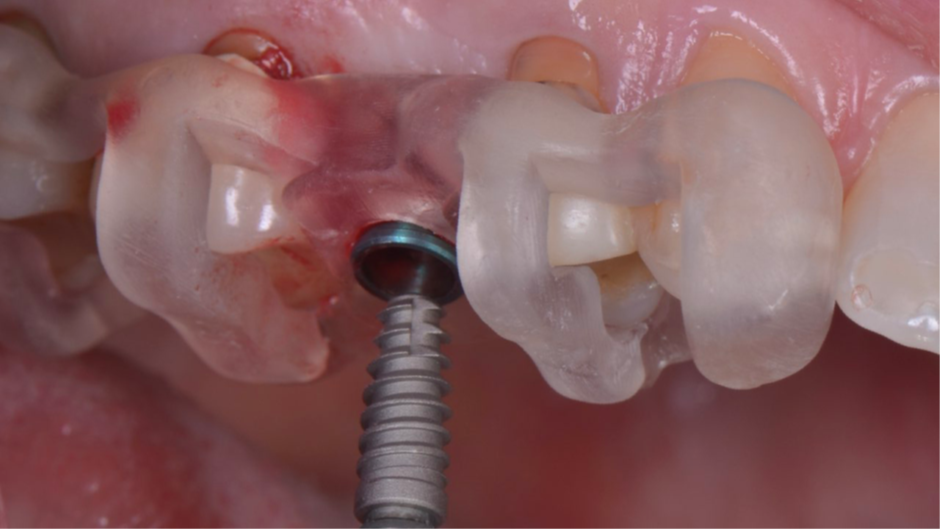

A coroa provisória foi fabricada por impressão 3D para criar os mesmos contornos da face vestibular dos dentes adjacentes (Figura 10). Uma coifa provisória de titânio foi parafusada ao pilar ideale para captura da coroa provisória impressa.

Nesse momento, existia uma grande diferença entre o contorno vestibular da coroa provisória e a posição da margem da mucosa (Figura 11). Então, foi utilizado uma resina flow para a captura da coroa provisória (Figura 12). E posteriormente, foi realizada o acabamento e polimento (Figura 13) para termos um excelente perfil de emergência da coroa (Figura 14).

Figura 10 – Coroa provisória fabricada por impressão 3D.

Figura 11 – Diferença entre o contorno vestibular da coroa provisória e a posição da margem da mucosa.

Figura 12 – Captura da coroa provisória com resina flow.